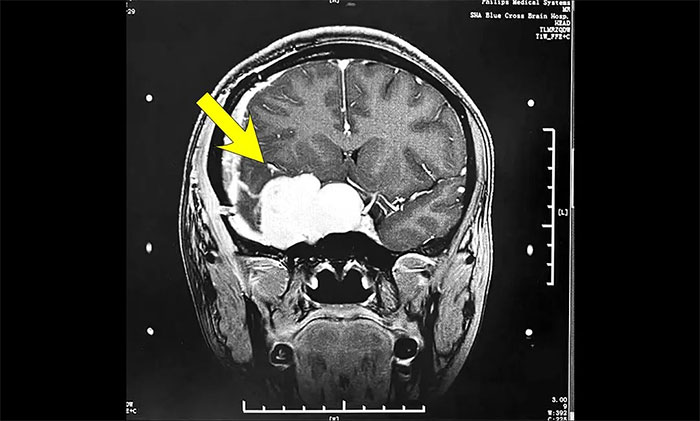

陈琦主任团队根据患者病情,精心设计了分期治疗的靶区和治疗剂量,用伽玛射线聚焦于病灶,使病变组织凋亡并逐渐阻断血供,从而达到治疗目的。完成治疗后患者顺利出院,半年后来院复查,病灶较前明显缩小。

▲ 治疗后病灶明显缩小